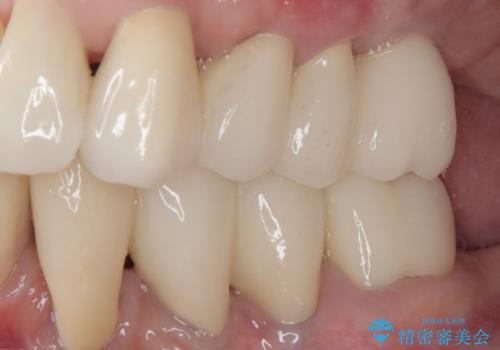

上顎口蓋からの堅い歯肉を移植する角化歯肉移植術を行いたかったのですが、体調不良から実施しなかったため、最終補綴物であるオールセラミッククラウンを装着した後に、知覚過敏や境目が見てしまうといった問題が一部で発生いたしました。

最終的には痛みや違和感のない状態にて治療を終えることができました。